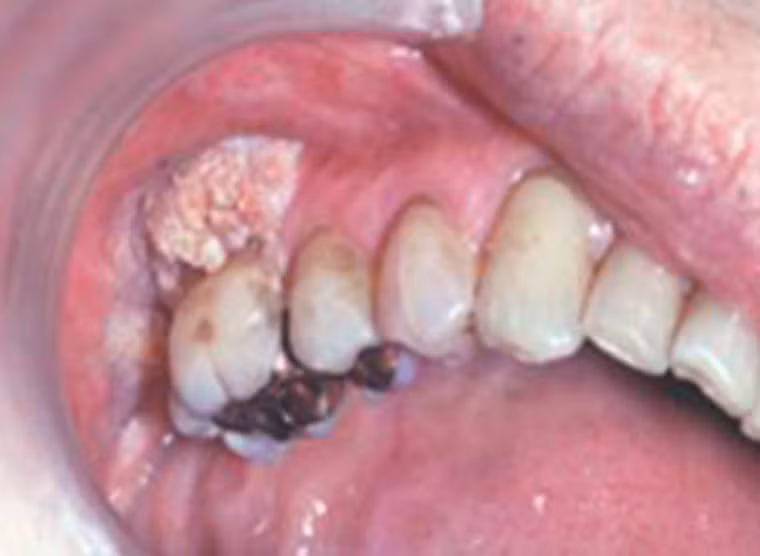

Nghiêm trọng hơn, người đàn ông này bị mắc ung thư biểu mô tế bào vảy dạng nhú. Khối u có màu trắng, gây lở loét. Nguyên nhân chính của căn bệnh cũng bắt nguồn từ thói quen hút thuốc lá.